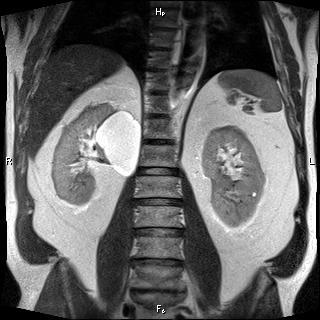

МРТ, или магнитно-резонансная томография, почек — это метод исследования, результатом которого является трёхмерное изображение органов с возможностью его послойного изучения в различных плоскостях. Он основан на способности ядер атомов откликаться на излучаемые аппаратом электромагнитные волны в условиях магнитного поля высокой напряжённости.

На снимках, полученных с помощью МРТ, отчётливо просматривается структура почек